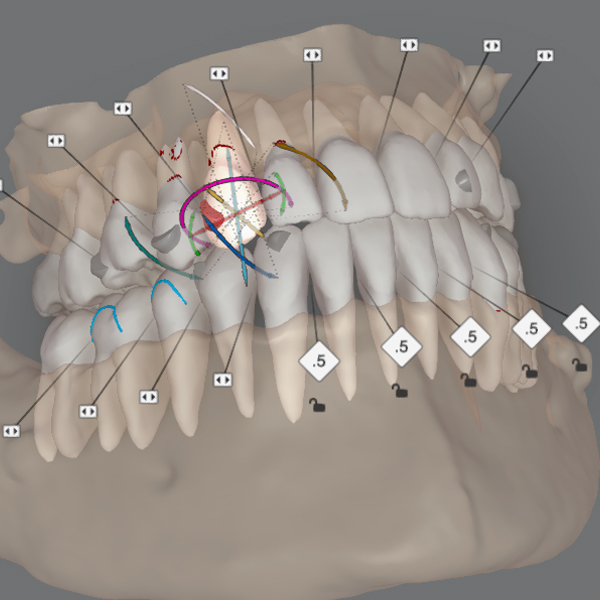

3D Scan and Detailed Explanation

We’ll take a 3D scan of your teeth using our iTero scanner. This allows us to give you a detailed view of your current alignment and provide a visual explanation of the proposed treatment. This advanced technology makes it easier for you to see what to expect from your orthodontic journey.

3D simulation , Video Simulation

We will share your 3D simulation called ClinCheck with you. We now have the technology to simulate your smile not only from your picture but also to create a video simulation, so you can get a detailed, Dynamic Smile Simulation from the treatment made.